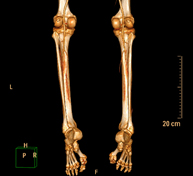

- TC d'ossos llargs Exploració radiològica que mitjançant un sistema de raigs X i detectors que giren al voltant del pacient i que reconstrueixen les imatges per ordinador (TC Multidetector), permet l'estudi detallat dels ossos llargs (tíbia, peroné, fèmur, húmer, radi i cúbit). Exploració radiològica que mitjançant un sistema de raigs X i detectors que giren al voltant del pacient i que reconstrueixen les imatges per ordinador (TC Multidetector), permet l'estudi detallat dels ossos llargs (tíbia, peroné, fèmur, húmer, radi i cúbit).

- Angio-TC arterial d'extremitats inferiors Prova diagnòstica no invasiva que consisteix en l'estudi vascular del sector aorto-ilíac i dels vasos arterials d'ambdues extremitats inferiors i l'obtenció d'imatges d'alta definició anatòmica mitjançant l'ús d'un equip de TC Multidetector d'última generació i de contrast iodat. La qualitat de les imatges permet realitzar reconstruccions en 2D i 3D gràcies a estacions de treball especialitzades en l'estudi arterial. Prova diagnòstica no invasiva que consisteix en l'estudi vascular del sector aorto-ilíac i dels vasos arterials d'ambdues extremitats inferiors i l'obtenció d'imatges d'alta definició anatòmica mitjançant l'ús d'un equip de TC Multidetector d'última generació i de contrast iodat. La qualitat de les imatges permet realitzar reconstruccions en 2D i 3D gràcies a estacions de treball especialitzades en l'estudi arterial.

- Angio TC arterial d'extremitats inferiors Prova diagnòstica no invasiva que consisteix en l'estudi de vascular del sector aorto-ílíac i dels vasos arterials d'ambdues extremitats inferiors amb l'obtenció d'imatges d'alta definició anatòmica mitjançant l'ús d'un equip de TC (Tomografia Computaritzada) i contrast iodat. La qualitat de les imatges permet realitzar reconstruccions en 2D i 3D gràcies a estacions de treball especialitzades en l'estudi arterial. Prova diagnòstica no invasiva que consisteix en l'estudi de vascular del sector aorto-ílíac i dels vasos arterials d'ambdues extremitats inferiors amb l'obtenció d'imatges d'alta definició anatòmica mitjançant l'ús d'un equip de TC (Tomografia Computaritzada) i contrast iodat. La qualitat de les imatges permet realitzar reconstruccions en 2D i 3D gràcies a estacions de treball especialitzades en l'estudi arterial.